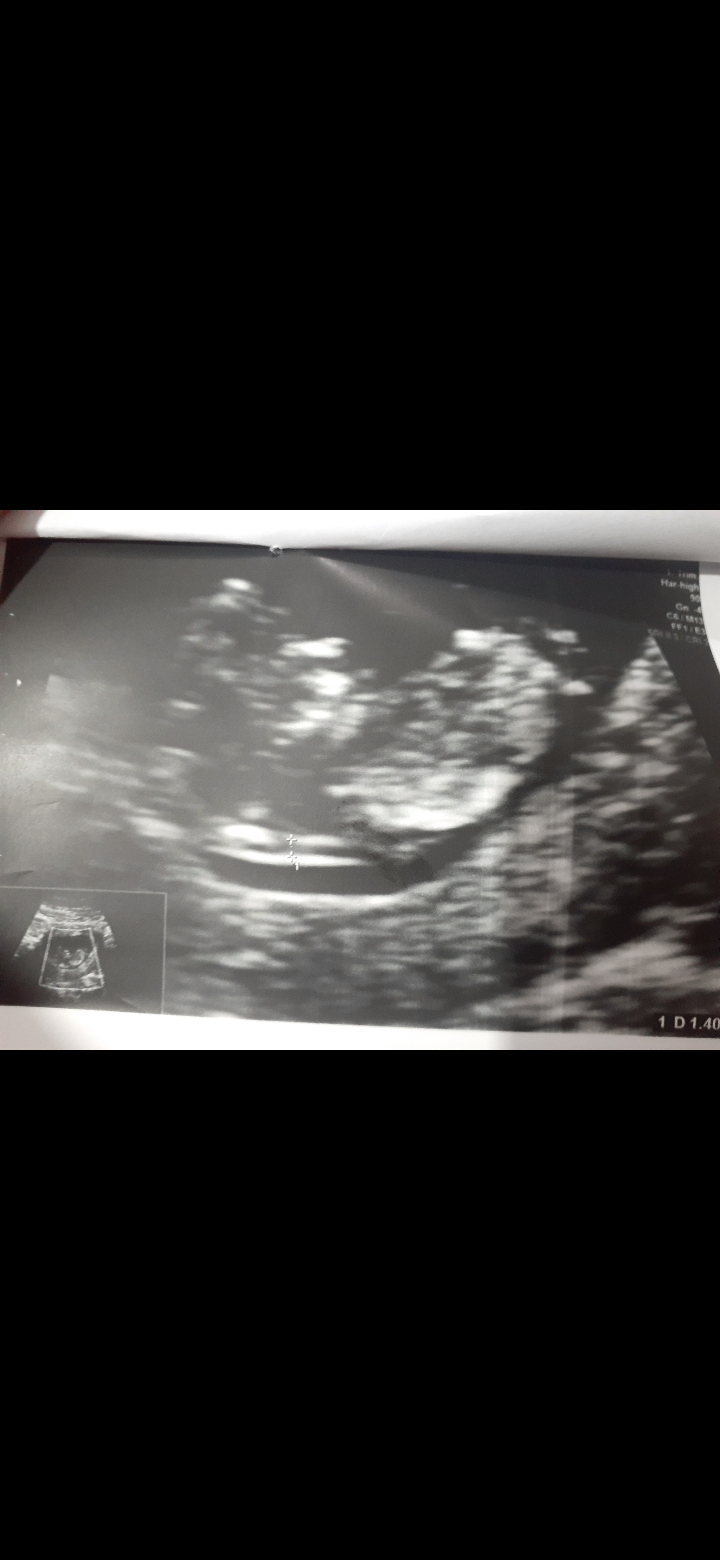

تعیین جنسیت

سلام بچه ها میتونید بگید از روی سونو بچم دختره یا پسر؟؟

سونوی ان تی

البته به من احتمال ضعیف گفت چیه میخوام تجربیات شمارم بدونم😄

دختره، جفت و ضربان قلبش هم بگو

ضربان قلب ۱۶۹

برای جفتش توضیحش رو میگم خودم سر درنمیارم چیه

نوشته:جایگزینی جفت خلفی گرید ۰ می باشد